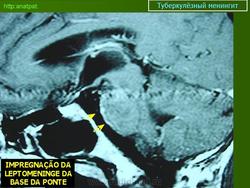

Менингеальный больной туберкулёзом на фоне ВИЧ.

anatpat.unicamp